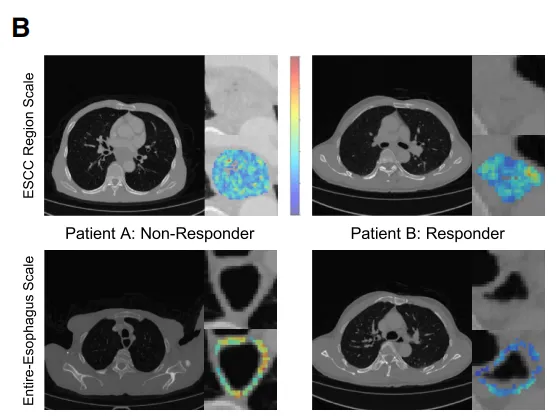

Fig 5 CT与病理学模态的多尺度可解释性

评估了CT影像特征在整个食管和 ESCC 特异性尺度上的预测贡献(图5A)。关键特征,如肿瘤区域内的大面积强调和食管区域内的大面积高灰度强调,被发现对治疗成功具有最大影响,且与治疗成功呈负相关。

可视化分析显示,非病理完全缓解(non-pCR)患者的灰度值升高,肿瘤及瘤周区域增强更为显著(图5B),这表明存在与治疗反应相关的独特影像学特征。接下来,针对组织学数据,我们在 WSI 、切片和细胞尺度上评估了模型的可解释性。基于注意力机制的热图识别出 WSI 上的预测区域(图5C),模型主要关注鳞状细胞癌周围淋巴细胞浸润区域。为进一步探究这一点,我们研究了切片层面的详细形态学特征与免疫治疗结果之间的关系。高注意力区域聚类显示局部组织结构(图5D)。由多模态大语言模型生成的这些切片层面特征的描述与 WSI 观察结果一致,确保了组织学数据的客观和自动化解读。